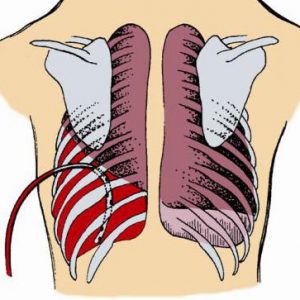

Hemotórax

El objetivo del tratamiento es estabilizar al paciente, detener el sangrado y extraer la sangre y el aire del espacio pleural. Se introduce una sonda pleural a través de la pared del tórax con el fin de drenar la sangre y el aire. La sonda se deja puesta durante varios días para volver a expandir el pulmón.

Cuando un hemotórax es grave y el sangrado no se puede controlar con una sonda pleural sola, se puede necesitar cirugía (toracotomía) para detener la hemorragia. Se debe igualmente tratar la causa del hemotórax. En personas que hayan tenido una lesión, con frecuencia todo lo que se necesita es un drenaje con sonda pleural. A menudo no se requiere cirugía.